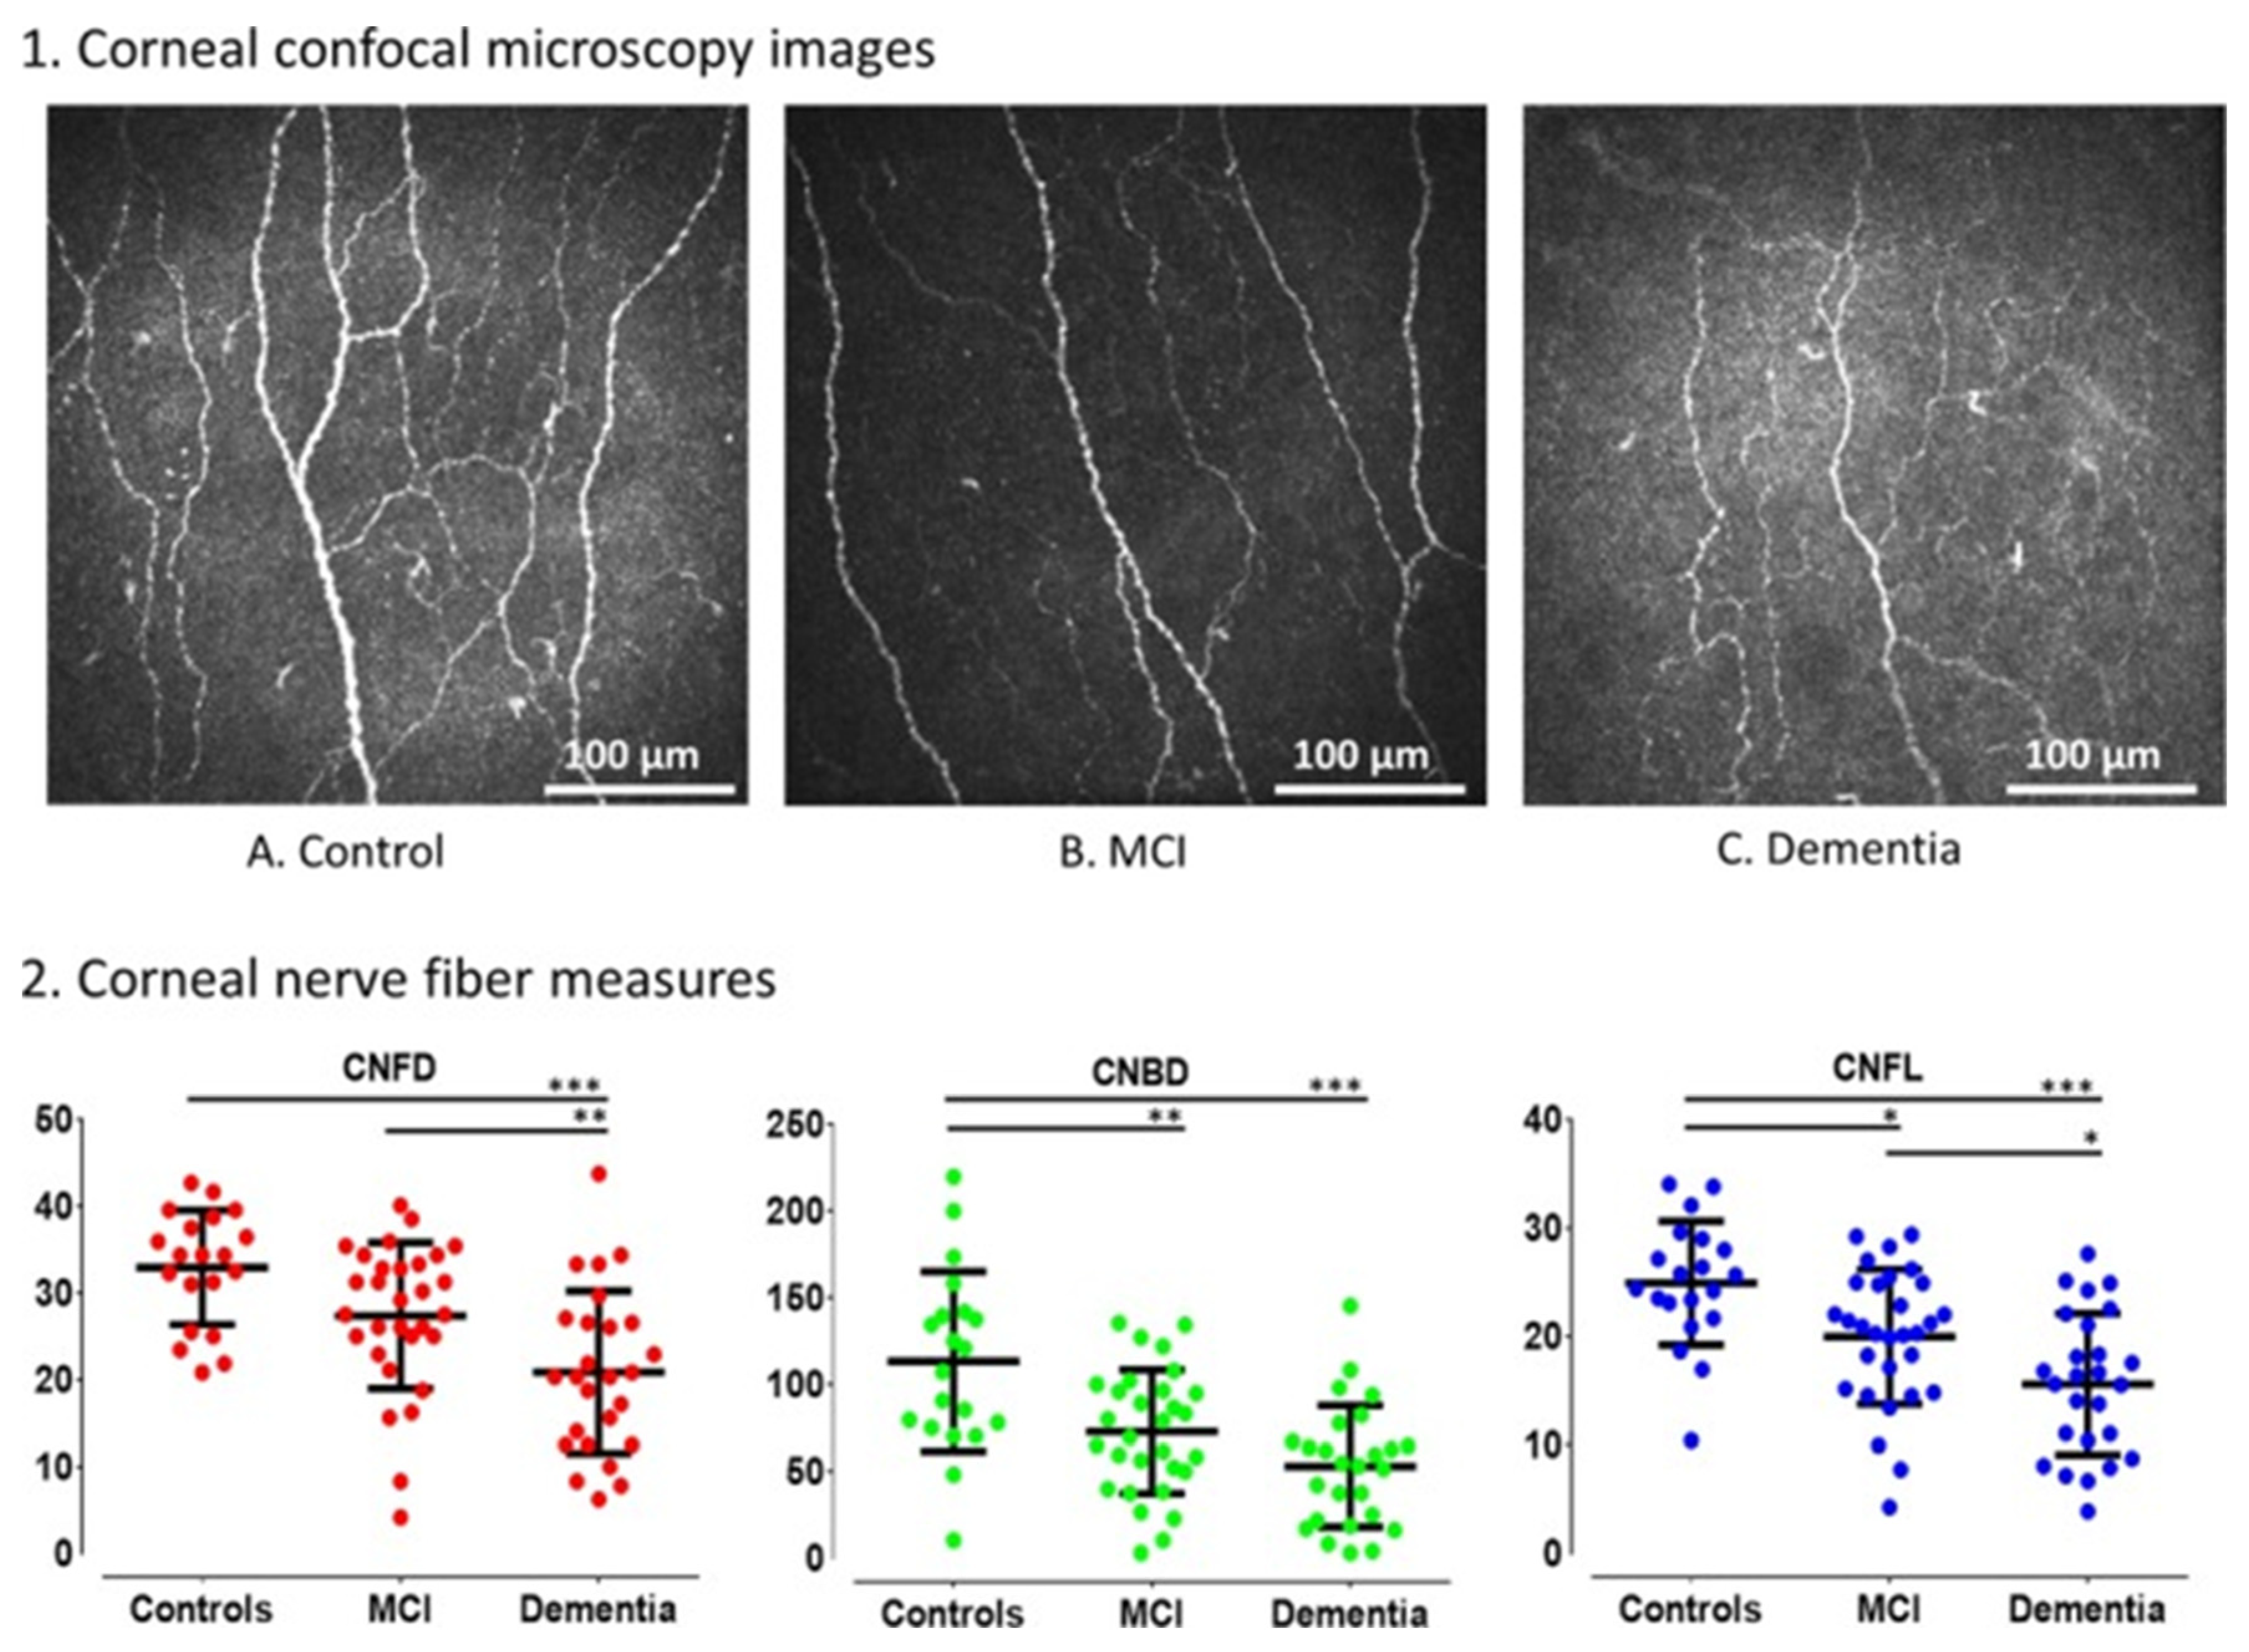

- Ponirakis, G.; Al Hamad, H.; Sankaranarayanan, A.; Khan, A.; Chandran, M.; Ramadan, M.; Tosino, R.; Gawhale, P.V.; Alobaidi, M.; AlSulaiti, E.; et al. Association of Corneal Nerve Fiber Measures with Cognitive Function in Dementia. Ann. Clin. Transl. Neurol. 2019, 6, 689–697. [Google Scholar] [CrossRef] [PubMed]

- Al-Janahi, E.; Ponirakis, G.; Al Hamad, H.; Vattoth, S.; Elsotouhy, A.; Petropoulos, I.N.; Khan, A.; Gad, H.; Chandran, M.; Sankaranarayanan, A.; et al. Corneal Nerve and Brain Imaging in Mild Cognitive Impairment and Dementia. J. Alzheimer’s Dis. 2020, 77, 1533–1543. [Google Scholar] [CrossRef]

- Ponirakis, G.; Al Hamad, H.; Omar, D.A.M.; Petropoulos, I.N.; Khan, A.; Gad, H.; Chandran, M.; Gadelseed, M.; Elsotouhy, A.; Ramadan, M.; et al. Corneal Nerve Loss Predicts Dementia in Patients with Mild Cognitive Impairment. Ann. Clin. Transl. Neurol. 2023, 10, 599–609. [Google Scholar] [CrossRef]

| Alzheimer’s Disease | Decreased corneal sensitivity Reduction in corneal nerve fiber density Corneal nerve branch density Corneal nerve fiber length | Cochet–Bonnet esthesiometer IVCM | Ornek et al. [31] Al-Janahi et al. [33] Ponirakis et al. [32] | |